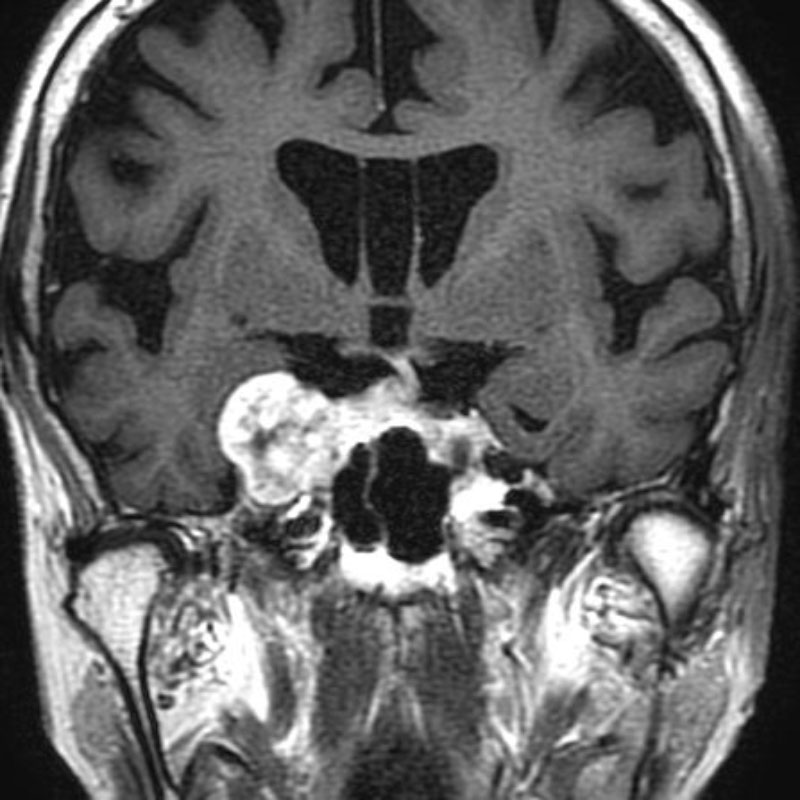

520

'24年3月

40代

小脳上衣腫

頭蓋内腫瘍摘出術

No.’24_22 手術前1

No.’24_22 手術前2